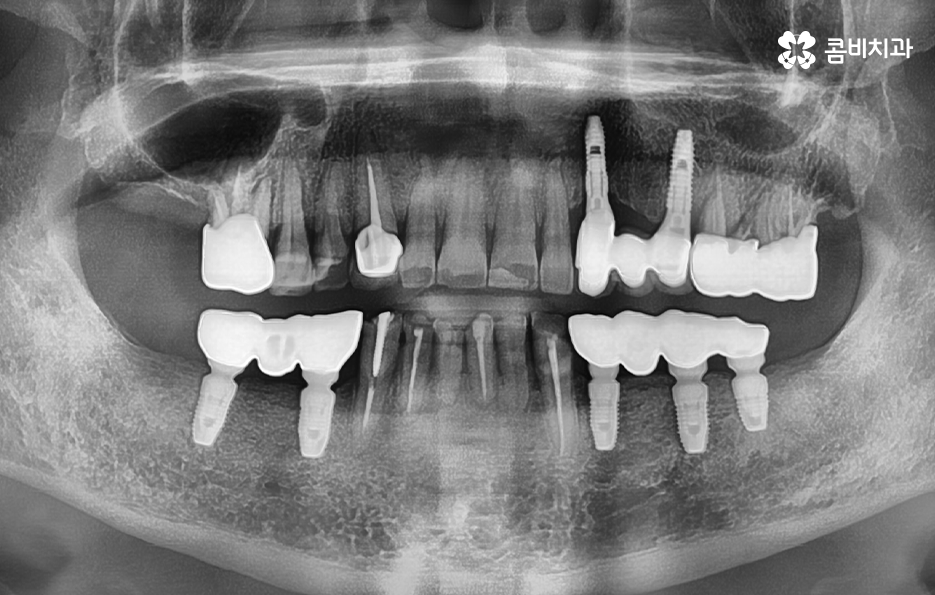

위 사진에서 보시는 것처럼 이미 치주염으로 인해 뿌리가 흔들리는 치아는 한꺼번에 여러 치아를 잃게 되었으며 기존의 임플란트 역시도 약해진 잇몸 뼈와 치료 비용 등을 감안하여 브릿지의 형태로 임플란트가 식립되어 있는 것을 확인할 수 있어요

실제 60대 이후 환자 분들의 경우 치주염으로 인해 잇몸 뼈가 녹아서 치아의 윗니, 아랫니 모두를 잃고 임플란트를 알아보시는 경우도 많으며 빠르면 50대에도 이러한 케이스의 환자분들을 볼 수 있는데요